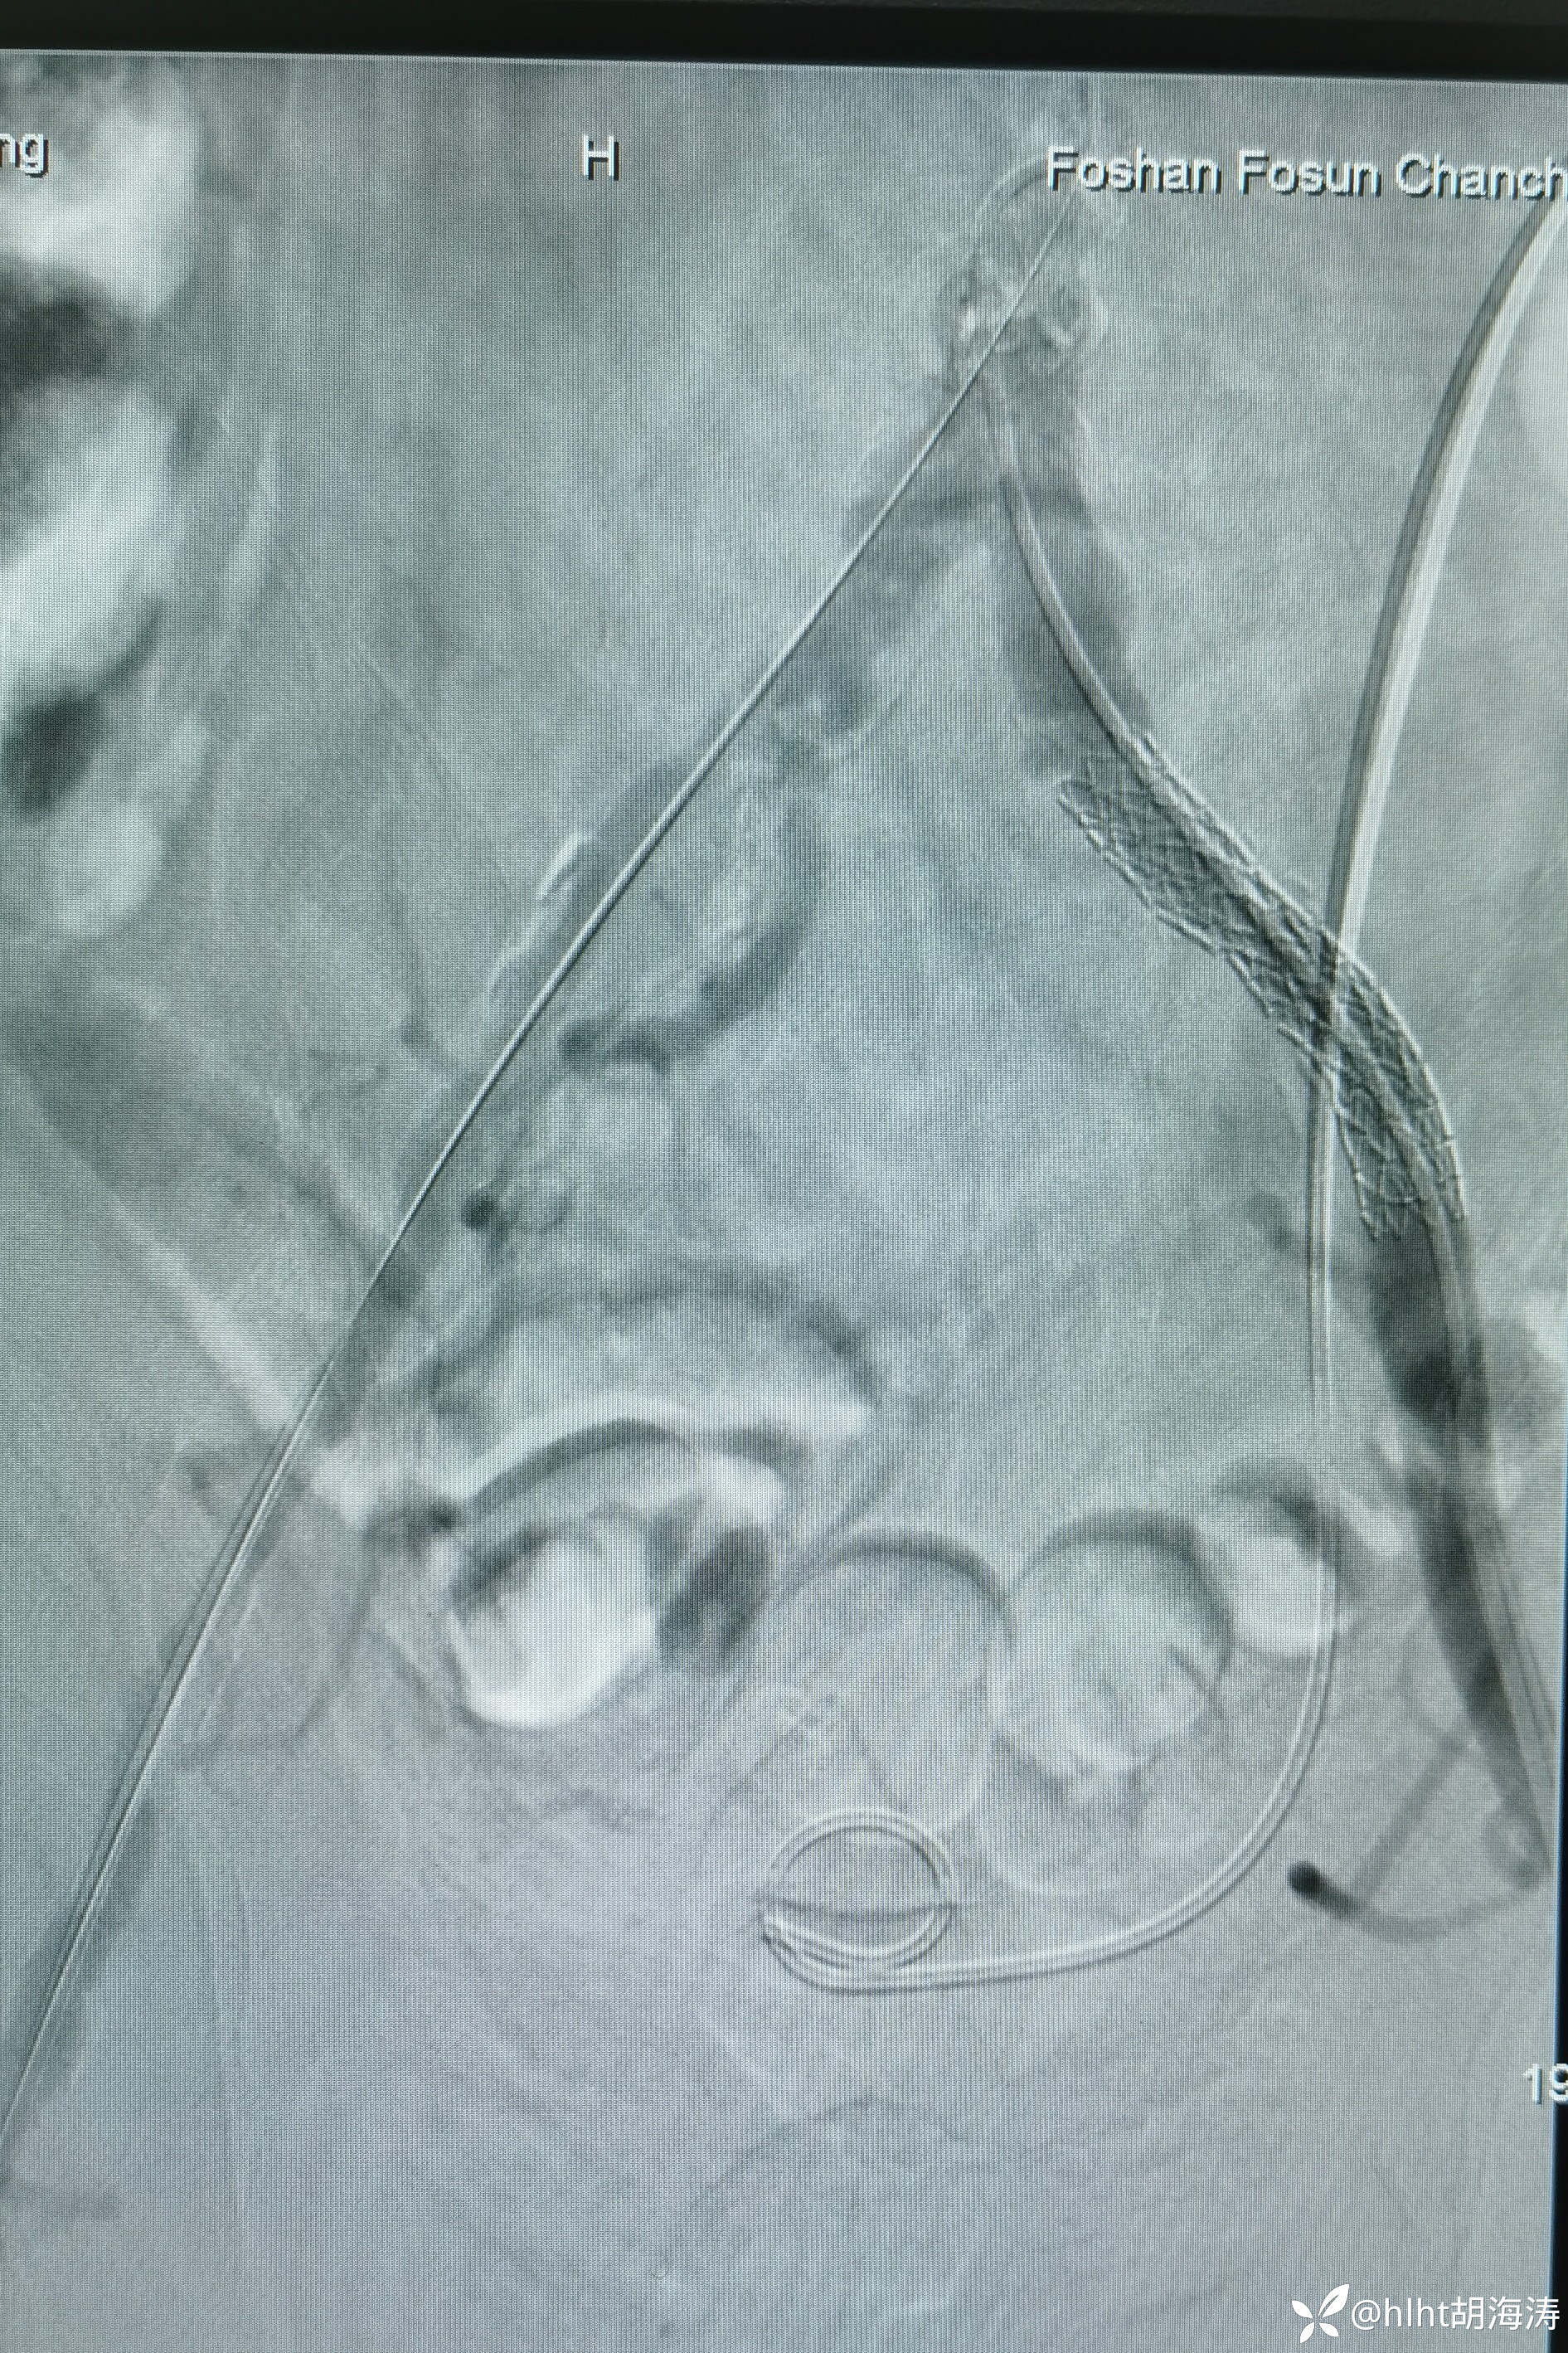

术中双侧髂外重度狭窄和右侧股浅动脉远端闭塞:

左侧髂外球囊扩张成形,然后10mm球扩支架,血流好,但是右侧血流慢

多次尝试,翻山,导丝没法进入左髂外,然后右侧腹股沟区穿刺:微创针

置入5F血管鞘:造影提示右侧髂外开口处重度狭窄

右侧髂外动脉直径不到左侧的1/2,扩到5mm,血流好,无限流夹层